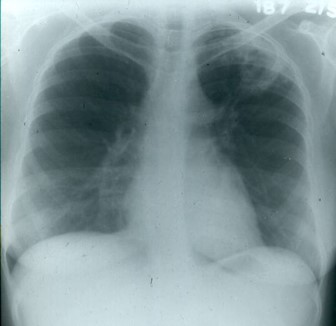

Pulmonary infection with nocardia may mimic tuberculosis in all of its forms (cavitary,

miliary, or nodular infiltrates) and/or tumor (mass lesions) as seen in the two presented

cases - the one on the left with a cavitating mass lesion, the one on the right with

an apical cavitary lesion.